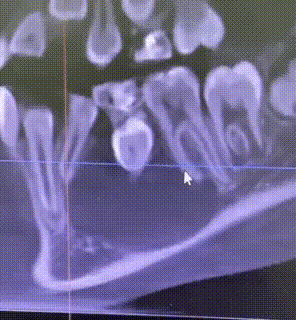

Вот так выглядит эта навигация: